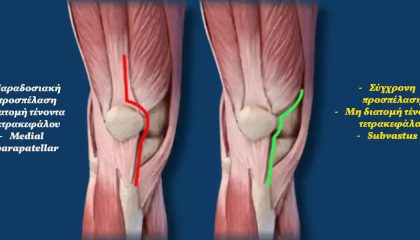

Η συνεχής αναζήτηση νέων καινοτόμων αλλά και αξιόπιστων λύσεων και τεχνικών στον χώρο των αρθροπλαστικών γόνατος και ισχίου, μας έχει οδηγήσει στην ευχάριστη θέση να έχουμε εισάγει στην Ορθοπαιδική Χειρουργική στον Ελληνικό χώρο πολλαπλές νέες λύσεις και χειρουργικές τεχνικές

Μια νέα προσέγγιση και θεωρία με εξατομίκευση της ευθυγράμμισης των προθέσεων για την αρθροπλαστική γόνατος